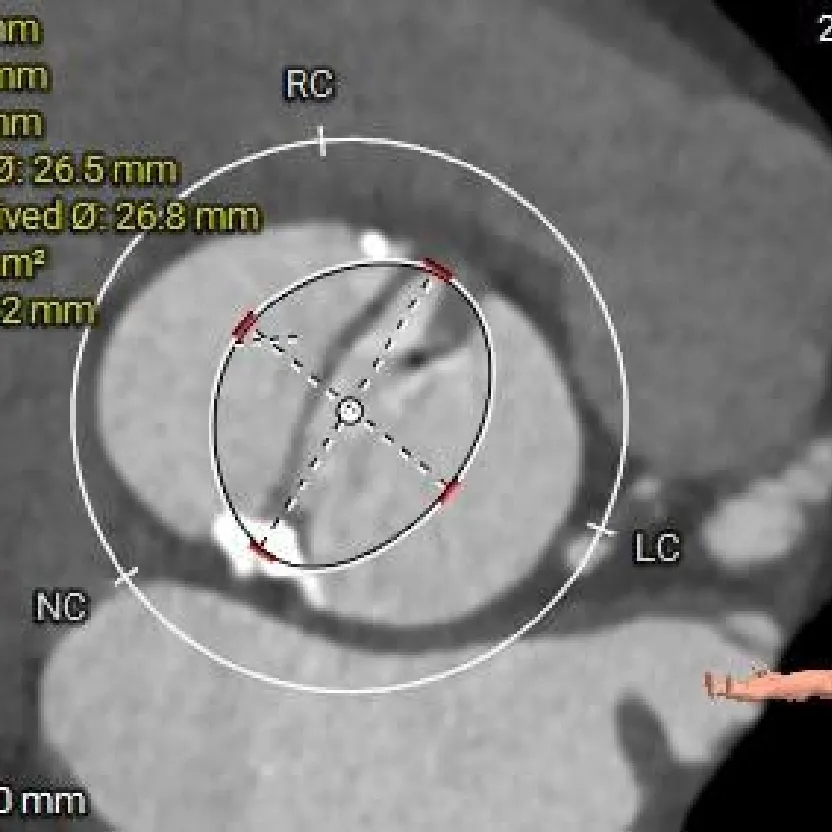

术前CT分析

TYPE-0型二叶瓣(纵列式),重度钙化,钙化分布不均匀,延伸至流出道可见,瓣叶明显增厚;

瓣环径约为24.0mm,流出道偏收口型,心室壁增厚,收缩期小心室;

左冠开口高度约为23.8mm,右冠开口高度约为27.0mm;

瓣环水平夹角47度,非横位心,升主动脉明显扩张;

主动脉根部测量

Annulus:24mm

LVOT:21.5mm

钙化积分:1396

SOV:30.6*43mm

STJ:41.9mm

AAO:51.2mm

瓣上结构测量

瓣上2mm

23.4mm

瓣上4mm

25.5mm

瓣上6mm

25.3mm

瓣上8mm

25mm

瓣上10mm

26.6mm

瓣上12mm

26.8mm

冠脉风险评估

LCA Height

RCA Height